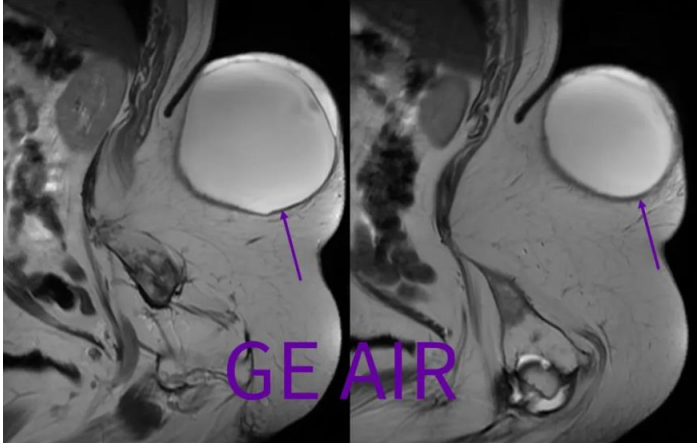

回顾性翻看矢状面T2和T2 fs,由于椎管内脂肪(红箭)和脑脊液交界,化学位移现象很重,所以干扰了囊性包膜的显示。

横断面三维CUBE T2和T1,具有薄层(1mm)高分辨的优势,可以最小化脑脊液流动伪影和化学位移伪影,有助于椎管内和/或邻近椎管区域的病变解剖显示,建议偶遇非常规病例的时候,加扫这么一个序列。 所谓,我为人人,人人为我。